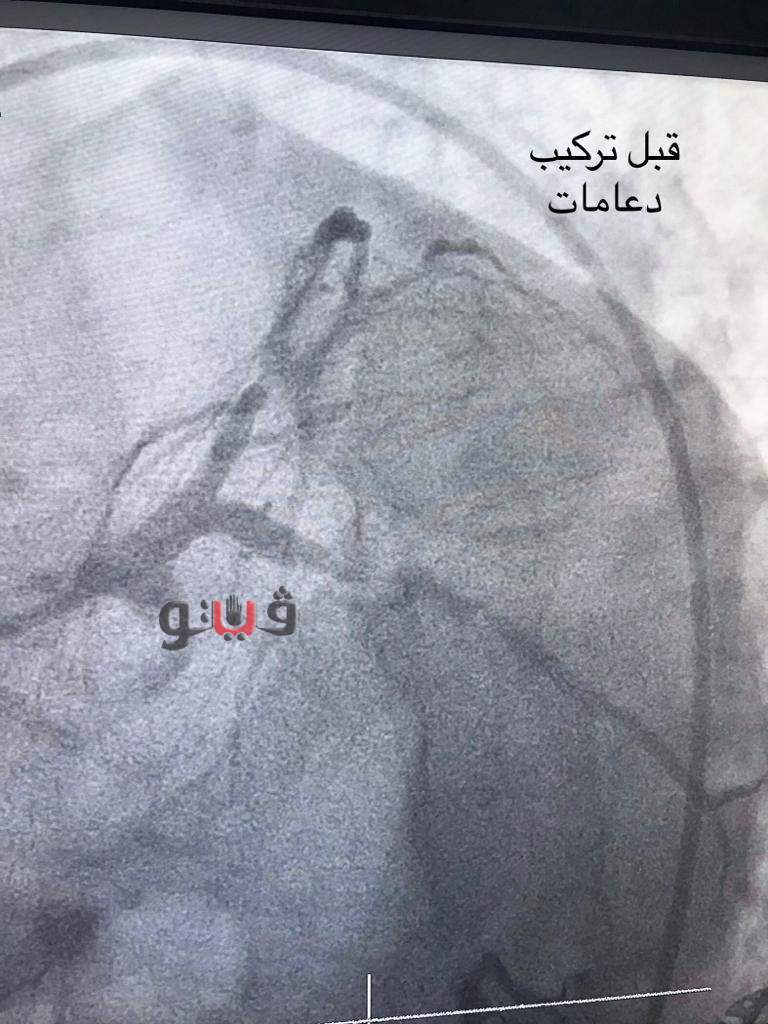

نجاح فريق طبي في تركيب دعامات دوائية لمريض بمستشفى المنصورة

أعلن اليوم الدكتور سعد مكى وكيل وزارة الصحة بالدقهلية عن انجاز جديد على يد ابطال صحة الدقهليه حيث نجح فريق طبي في إجراء قسطرة علاجية وتركيب دعامتين دوائيتين بالشريان الأمامي النازل ودعامة دوائية بالشريان المحوري لمريض يبلغ من العمر 65 عاما يعاني من وجود ضيق شديد وحرج بالشريان الأمامي النازل وانسداد مزمن كامل بالشريان المحوري مما ترتب عليه نقص كفاءة عضلة القلب و اجهاد شديد مع المجهود البسيط.

جاء ذلك بعد تعرضه لذبحات متكررة وفشلت جميع محاولات المريض لتركيب دعامات وتم تحويله لعمل جراحة قلب مفتوح ورفض المريض العملية وحضر لمستشفى المنصورة الدولي و تم عرضه على الفريق الطبى وتم مباشرته من خلال استشاري جراحة القلب واستشاري القسطرة واتخاذ القرار بتركيب ثلاث دعامات دوائية لتجنب عمل جراحة قلب مفتوح للمريض .

ونجحت عملية تركيب الدعامات وخرج المريض بصحة جيدة، واطمأن وكيل صحة الدقهلية على ان المريض بحالة مستقرة وجيده.